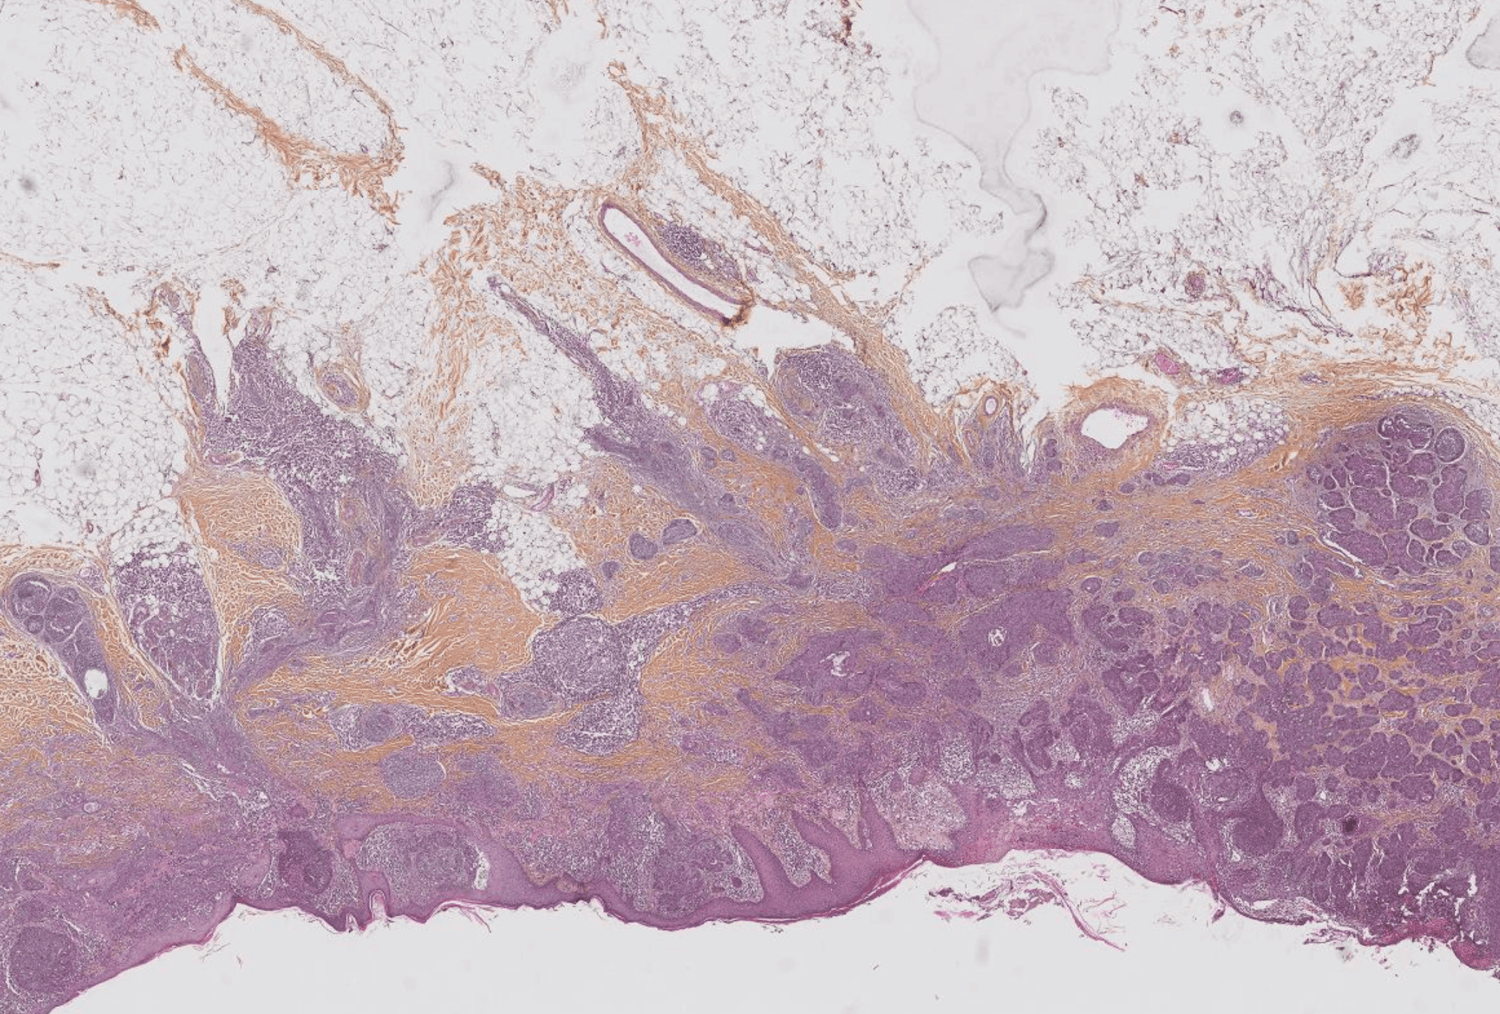

Automatic Detection and Measure of Malignant Lesion in WSI.

SQUAMOUS-CELL CARCINOMA, MELANOMA, BASAL-CELL CARCINOMA